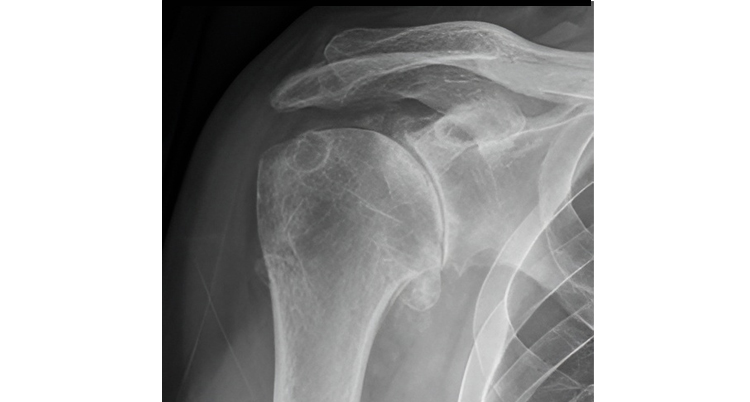

Shoulder osteoarthritis, anteroposterior X-ray. Hellerhoff, Wikimedia Commons, 2015. Licensed under CC BY-SA 4.0.

Shoulder Osteoarthritis

What is it: Shoulder osteoarthritis occurs when the cartilage that cushions the joint gradually wears down. This can affect the main ball and socket joint of the shoulder and often develops slowly over time.

Symptoms: People often describe a deep, aching shoulder pain, stiffness after periods of rest, and difficulty reaching overhead or behind the back. Symptoms may fluctuate, with periods of increased discomfort followed by improvement.

What to do: Physical therapy can help manage arthritis by improving joint mobility, strengthening the muscles that support the shoulder, and teaching strategies to reduce joint stress. While arthritis cannot be reversed, many people are able to remain active and functional with appropriate conservative care.